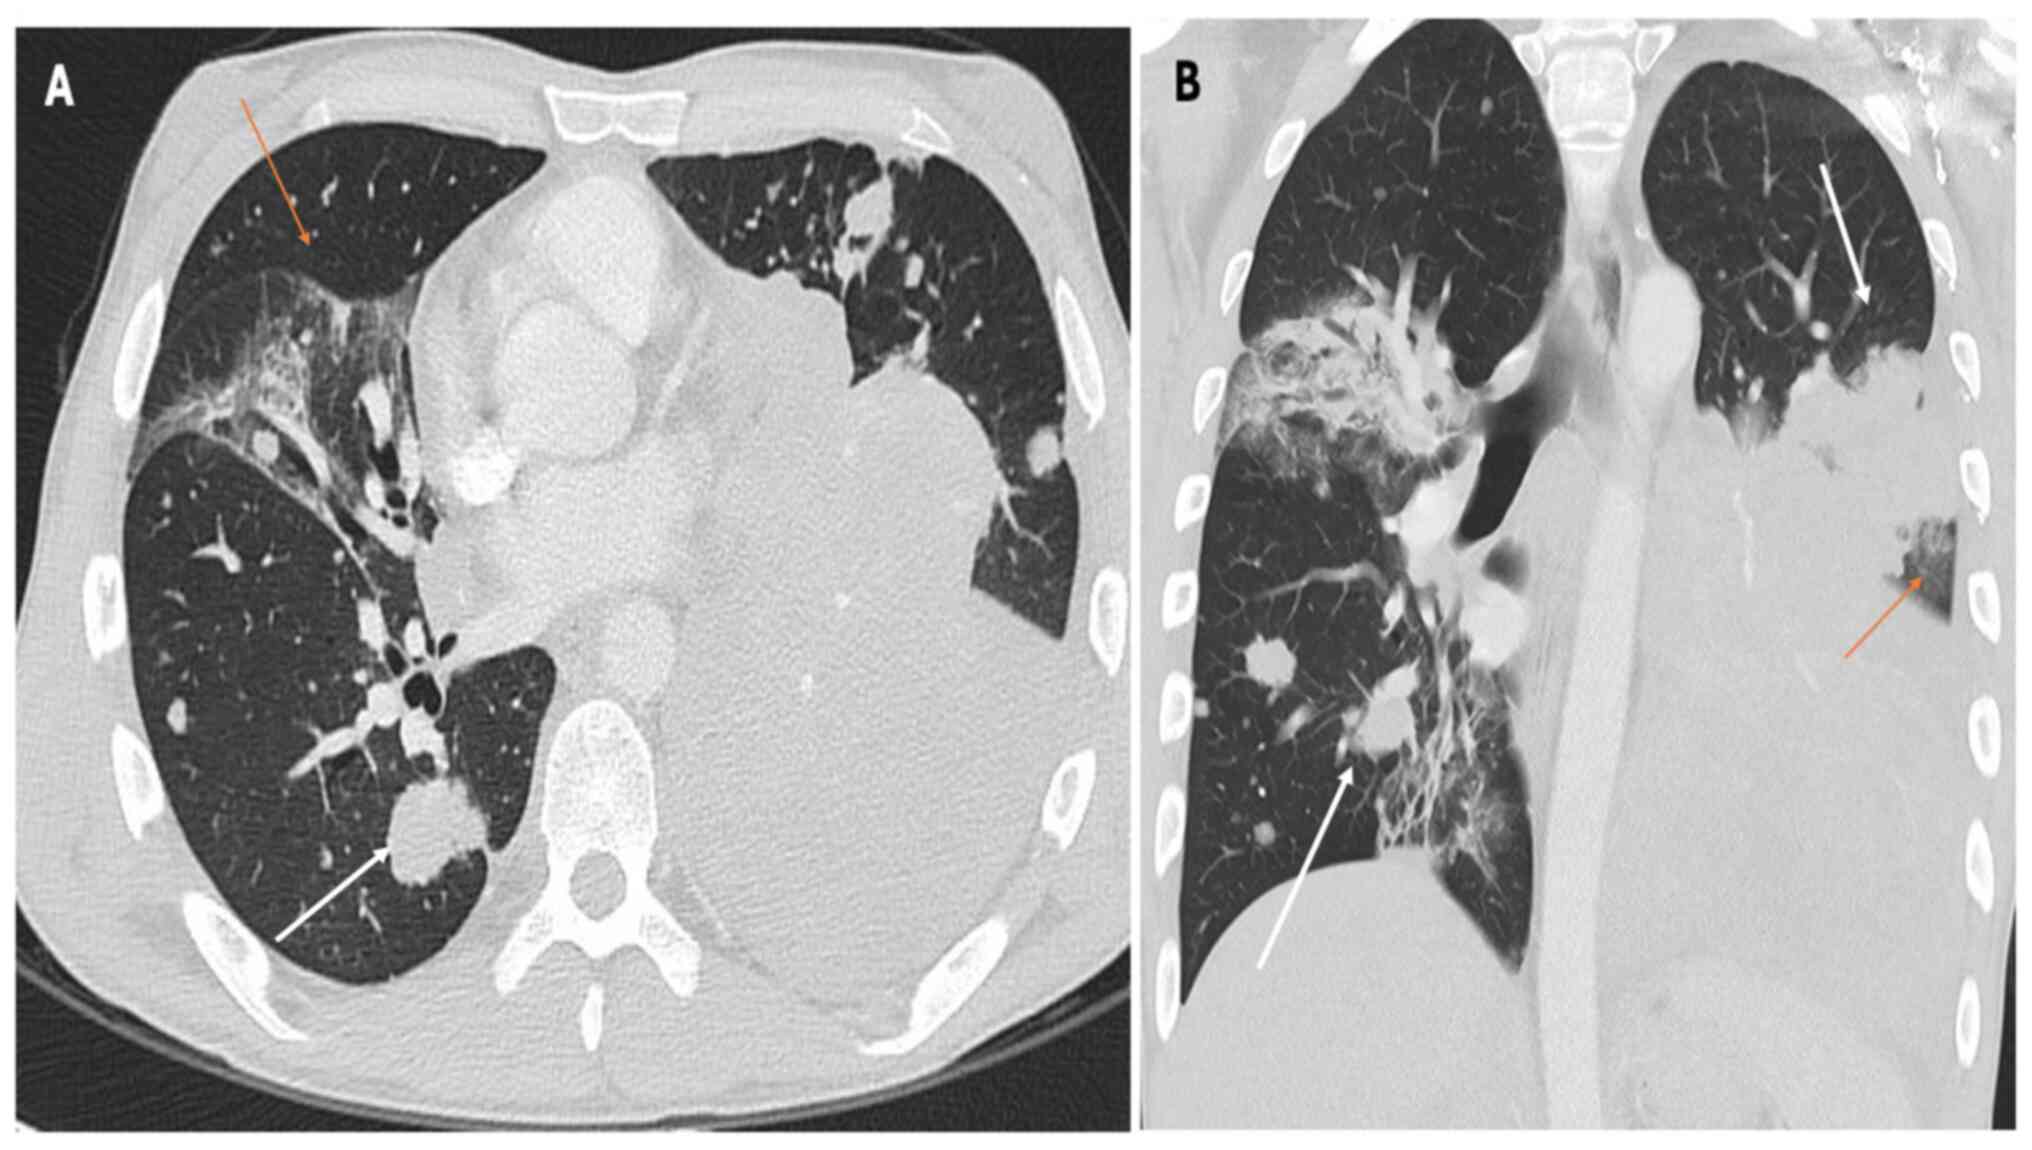

Pneumonitis is a rare irAE following ICI therapy, and it manifests as interstitial lung disease (36). Table II summarizes the main CT patterns observed in ICI-related pneumonitis. Pneumonitis secondary to ICI treatment presents in four distinct patterns: i) Organizing pneumonia (OP); ii) nonspecific interstitial pneumonia (NSIP); iii) hypersensitivity pneumonitis (HP); and iv) diffuse alveolar damage (DAD) (36). While chest X-ray findings in ICI-related pneumonitis may be nonspecific, characteristic abnormalities can aid the diagnostic process (37). Common radiographic manifestations include patchy or diffuse opacities, consolidations and interstitial infiltrates, which may be bilateral and involve multiple lung lobes (37,38). Additionally, air bronchograms or a ‘ground-glass’ appearance may suggest alveolar involvement and inflammatory changes within the lung parenchyma as shown in Fig. 2, Fig. 3 and Fig. 4, which report on a case of gastric, lung and rectal cancer, respectively. However, it is essential to recognize that chest X-ray findings alone may not be sufficient to diagnose or exclude pneumonitis (37) definitively. Further imaging with CT of the chest is often necessary to delineate the extent and nature of pulmonary abnormalities and guide subsequent management decisions (38).

Figure 3

(A) Axial and (B) coronal CT scans with lung parenchyma reconstruction revealed extensive ground-glass opacity predominantly distributed peripherally in the lower lung lobes, accompanied by interstitial septal thickening and more consolidated regions (see arrows). The consolidations are notably pronounced and extensive in the right lower lobe, confirming immunotherapy-induced pneumonia in a 58-year-old patient recently diagnosed with lung adenocarcinoma and undergoing osimertinib therapy.